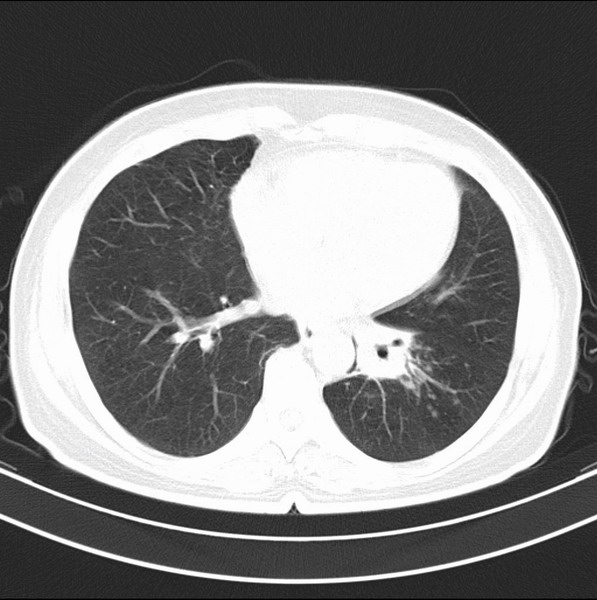

女、63

咳嗽、胸痛四个月

考虑左下肺中央型肺癌

支持左下中央型肺癌伴阻塞性炎症不张。

包绕左下肺基底段的不规则的软组织肿块,段支气管腔变形、狭窄及阻塞性炎症,病变区不规则强化,又是老年女性支持楼上看法。

考虑左肺下叶中央型肺癌伴阻塞性肺炎、支气管黏液嵌塞。

典型病例:左下肺基底段中央型肺癌,相应支气管狭窄并阻塞性炎症